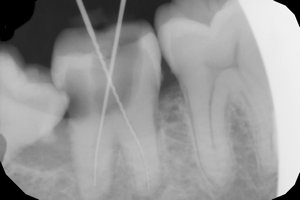

Мне 21 год. Год назад мне поставили химическую пломбу на 24 зуб. Пломба частично вывалилась, и как бы внутри зуба образовалась дырка, в которую постоянно попадала еда и гнила там. Через несколько месяцев я поставила новую пломбу, тоже химическую. Но возникла снова та же проблема.

Недавно я обращалась в несколько стоматологий. Мне сказали, что в зубе развивается кариес, и стенки его тонкие. Одни предлагали поставить штифт и новую светоотвердевающую пломбу. Другие говорили, что необходим штифт и коронка.